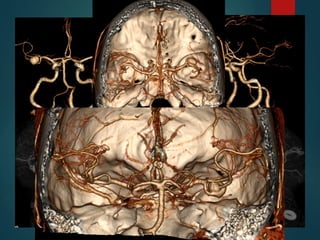

Patología Aneurismática

 Dilatación vascular que afecta solo una porción del

perímetro vascular.

 Carece de lámina elástica y ± túnica media.

 Se los clasifica básicamente en:

 Sacular;

 Ampollar;

 Fusiforme.

Patología Aneurismática  Dilataciónvascular que afecta solo una porción del perímetro vascular.  Carece de lámina elástica y ± túnica media.  Se los clasifica básicamente en:  Sacular;  Ampollar;  Fusiforme.

• 23.

Pericallosa 4% Comunicante Anterior30% Bifurcación ACI 7.5% ACM 20% Comunicante Posterior 25% Tope Basilar 7% PICA 3% Otras 3,5% Brisman, et al. N Engl J Med 2006;355:928-39.

Métodos diagnósticos  AngiografíaDigital (3D DSA); Sensibilidad del 96% lesiones del 0.5 a 4 mm.  TC, Angio TC (Multidetector); Sensibilidad del 40% al 97%.  Angio RM (T.O.F.) Sensibilidad 38% lesiones al 94%